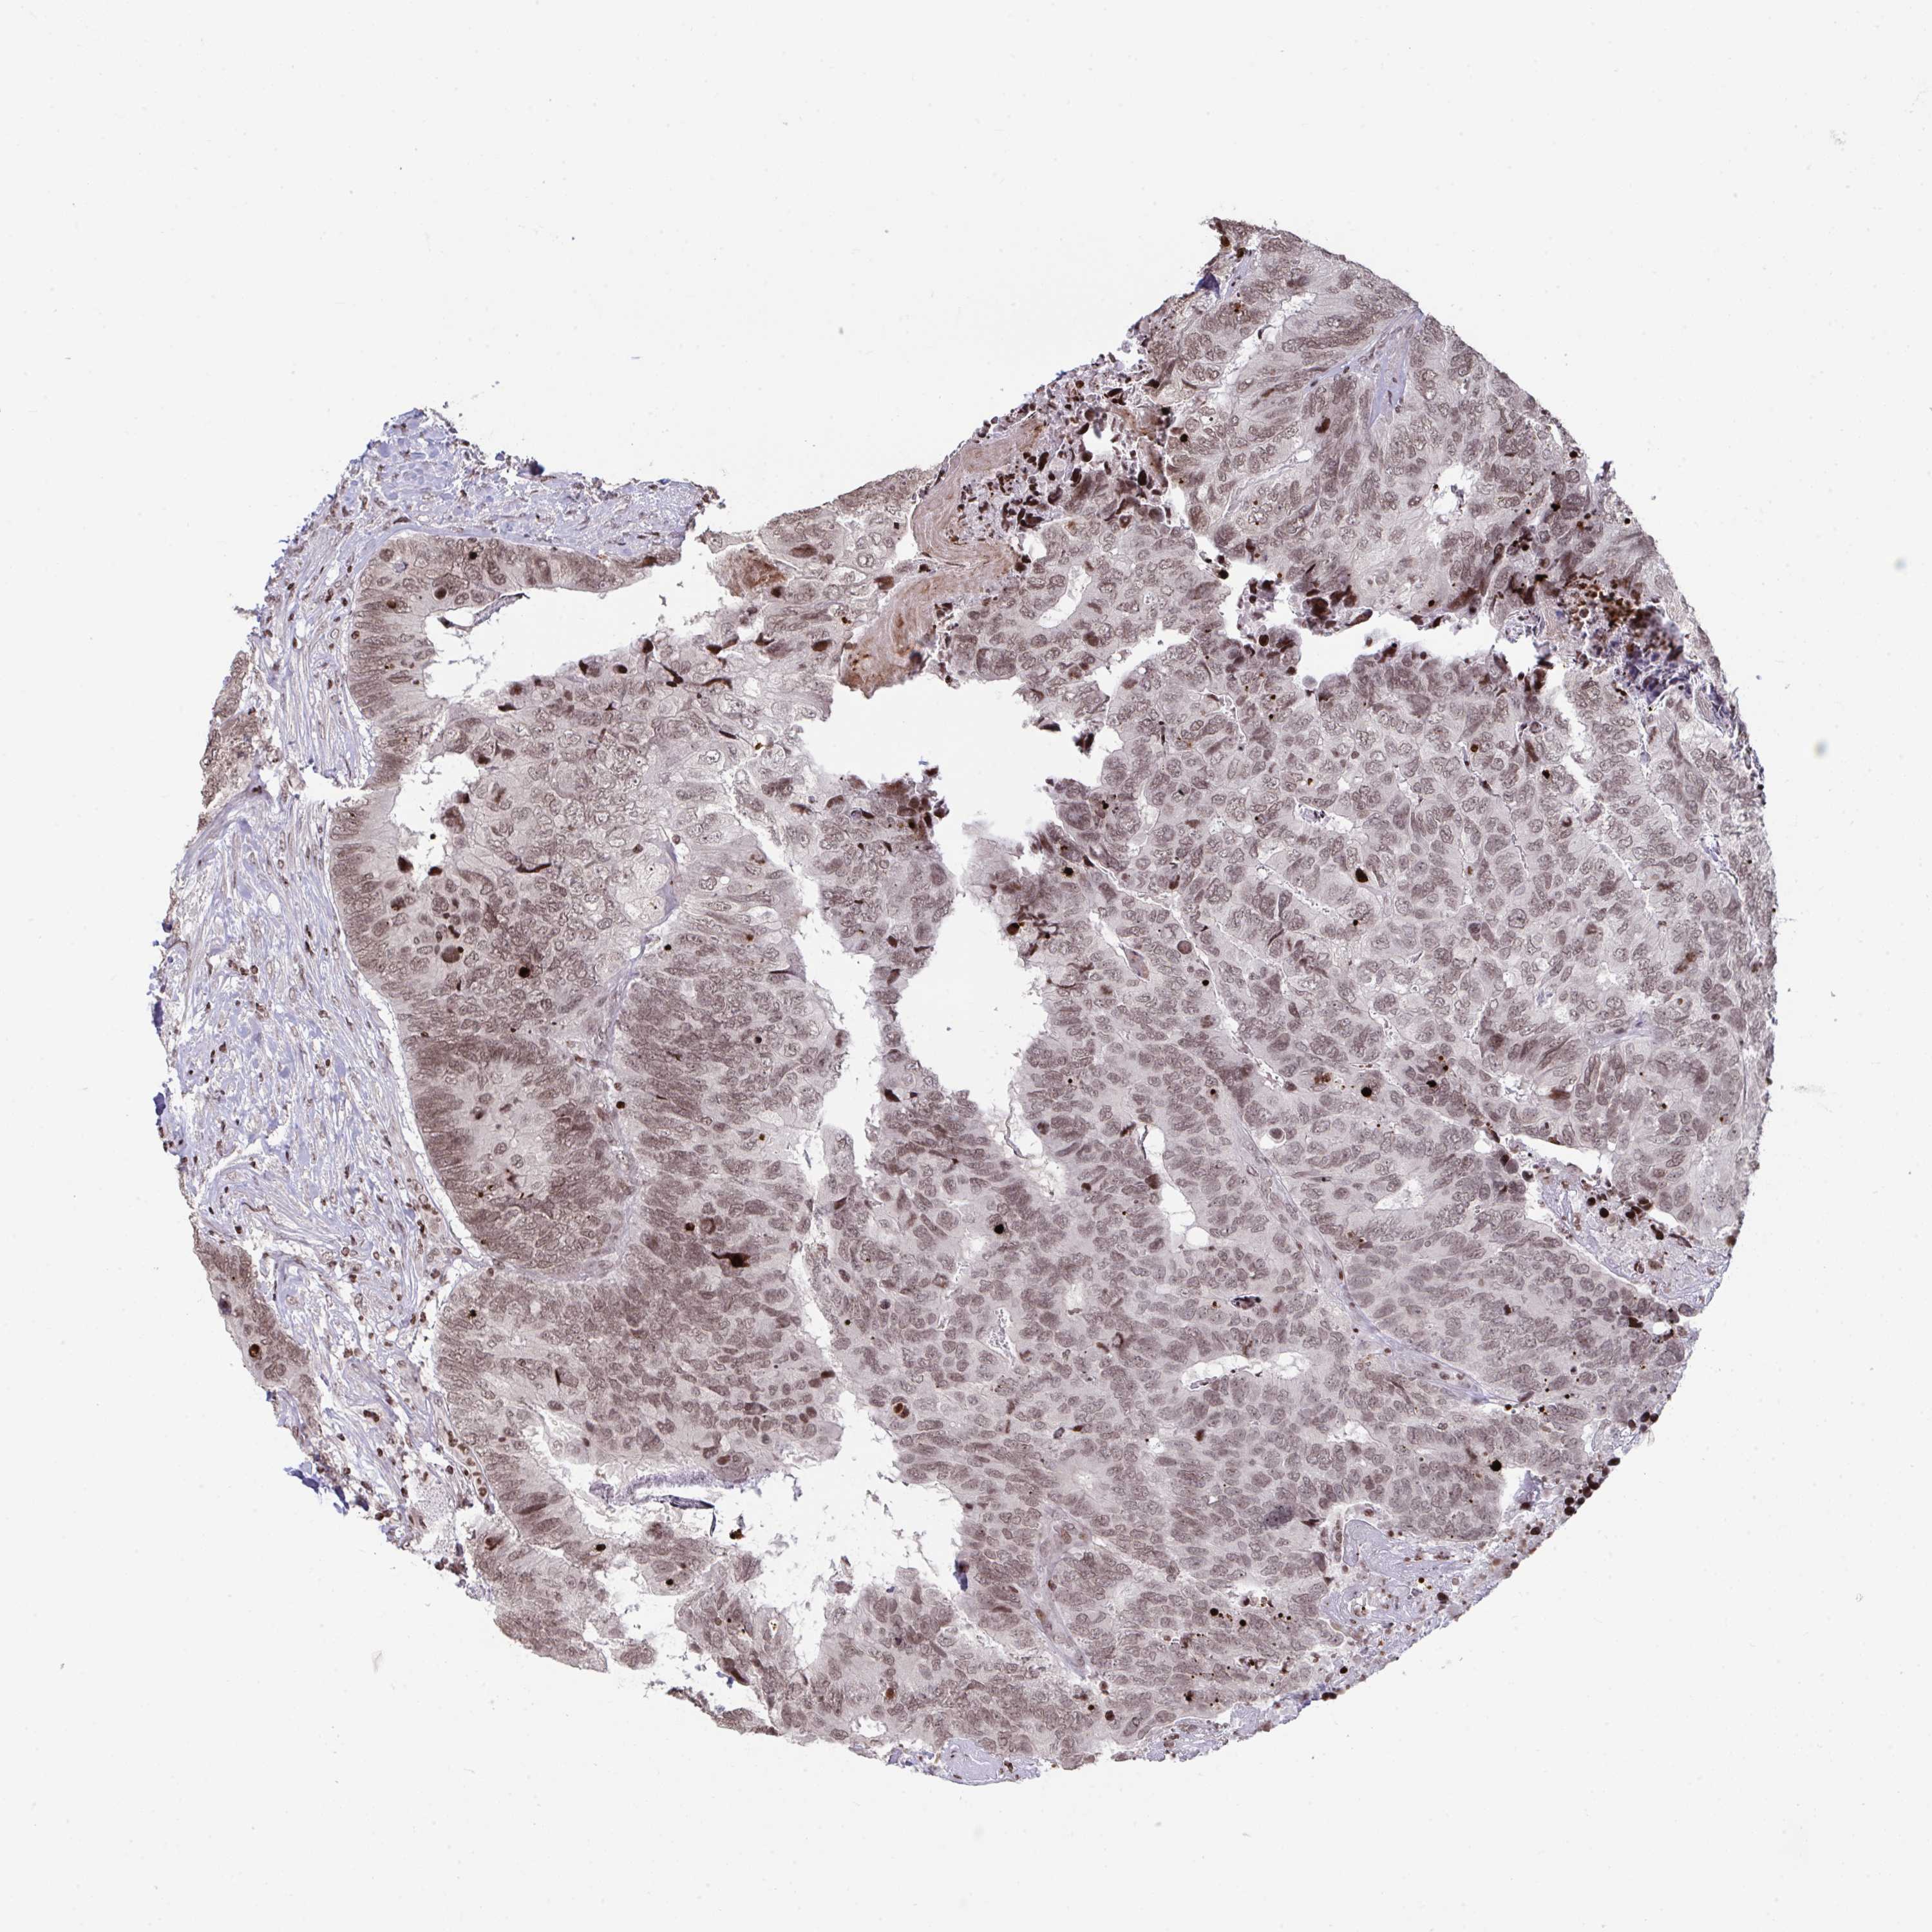

CANCER BREAST CANCER Show tissue menu

BRCA TCGA BRCA VALIDATION PROTEIN EXPRESSION

Breast cancer

Human cancer